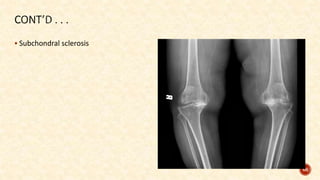

 Subchondral sclerosis